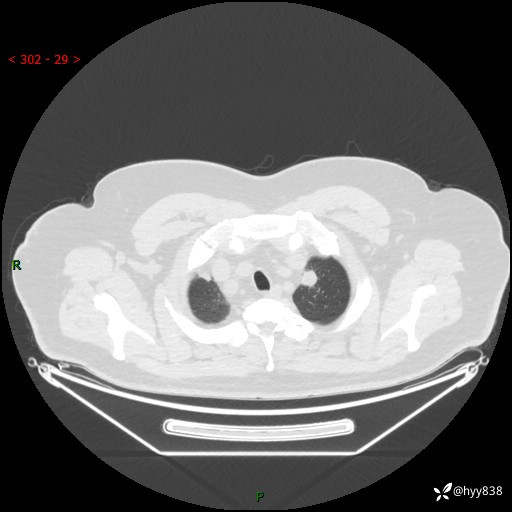

性别:男

年龄:48岁

简要病史:发热来诊(门诊病人)

胸部CT平扫